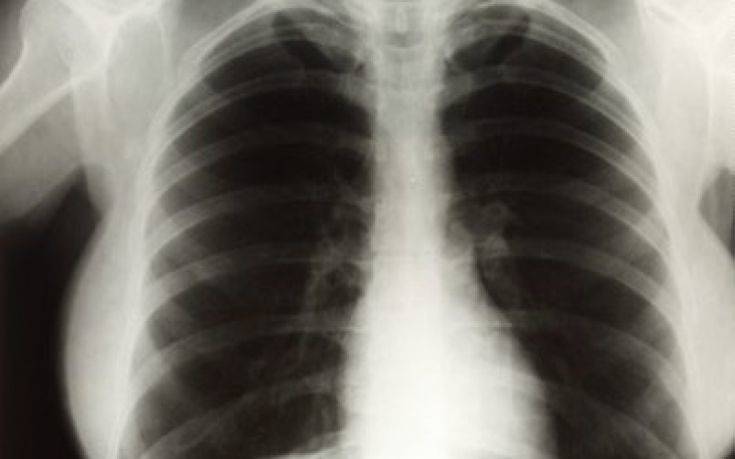

«Βρήκαμε ότι υπεισέρχεται σε μεγάλο βαθμό ο υποκειμενικός παράγοντας στην ερμηνεία της συγκεκριμένης ακτινογραφίας, κάτι που περιορίζει την αποτελεσματικότητά της», ανέφερε ο επικεφαλής ερευνητής της Google Health, Σράβια Σέτι.

«Η ερμηνεία των ακτινογραφιών των πνευμόνων συχνά γίνεται με υποκειμενικό τρόπο, κάτι προβληματικό από την οπτική γωνία της βαθιάς μάθησης. Καταφέραμε να παράγουμε ένα σύστημα που κάνει πιο αξιόπιστη αξιολόγηση», δήλωσε ο συνάδελφός του, Ντάνιελ Τσε.